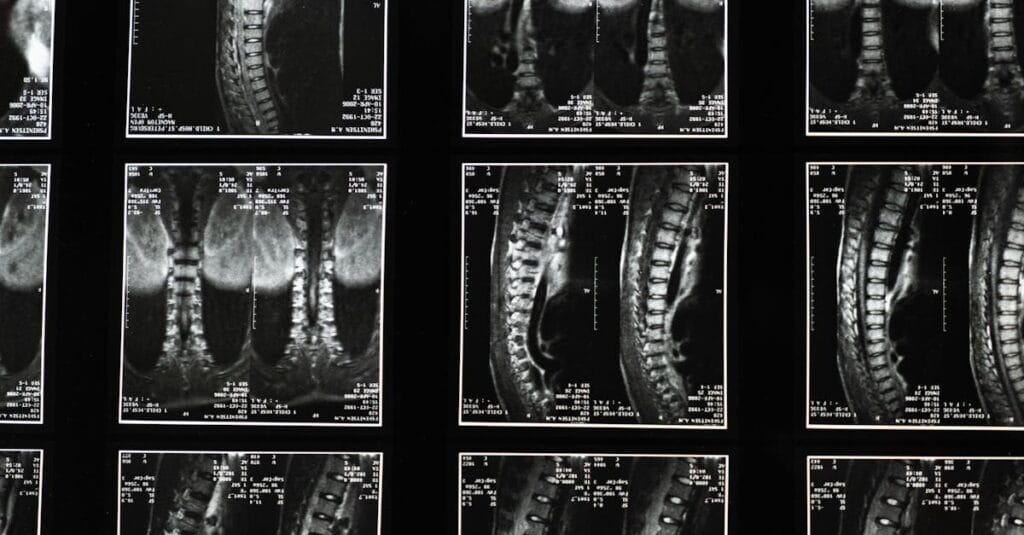

Before starting a decompression treatment, it is crucial to obtain an accurate diagnosis of the underlying condition. This includes thorough evaluations such as imaging examinations to identify the exact location of the problem. Once the diagnosis is established, the treatment can be tailored to effectively target sciatic pain.

Un examen clinique approfondi et des imageries comme une IRM ou une radiographie sont souvent nécessaires.

Une consultation clinique et des examens d’imagerie comme l’IRM sont nécessaires pour déterminer l’éligibilité.